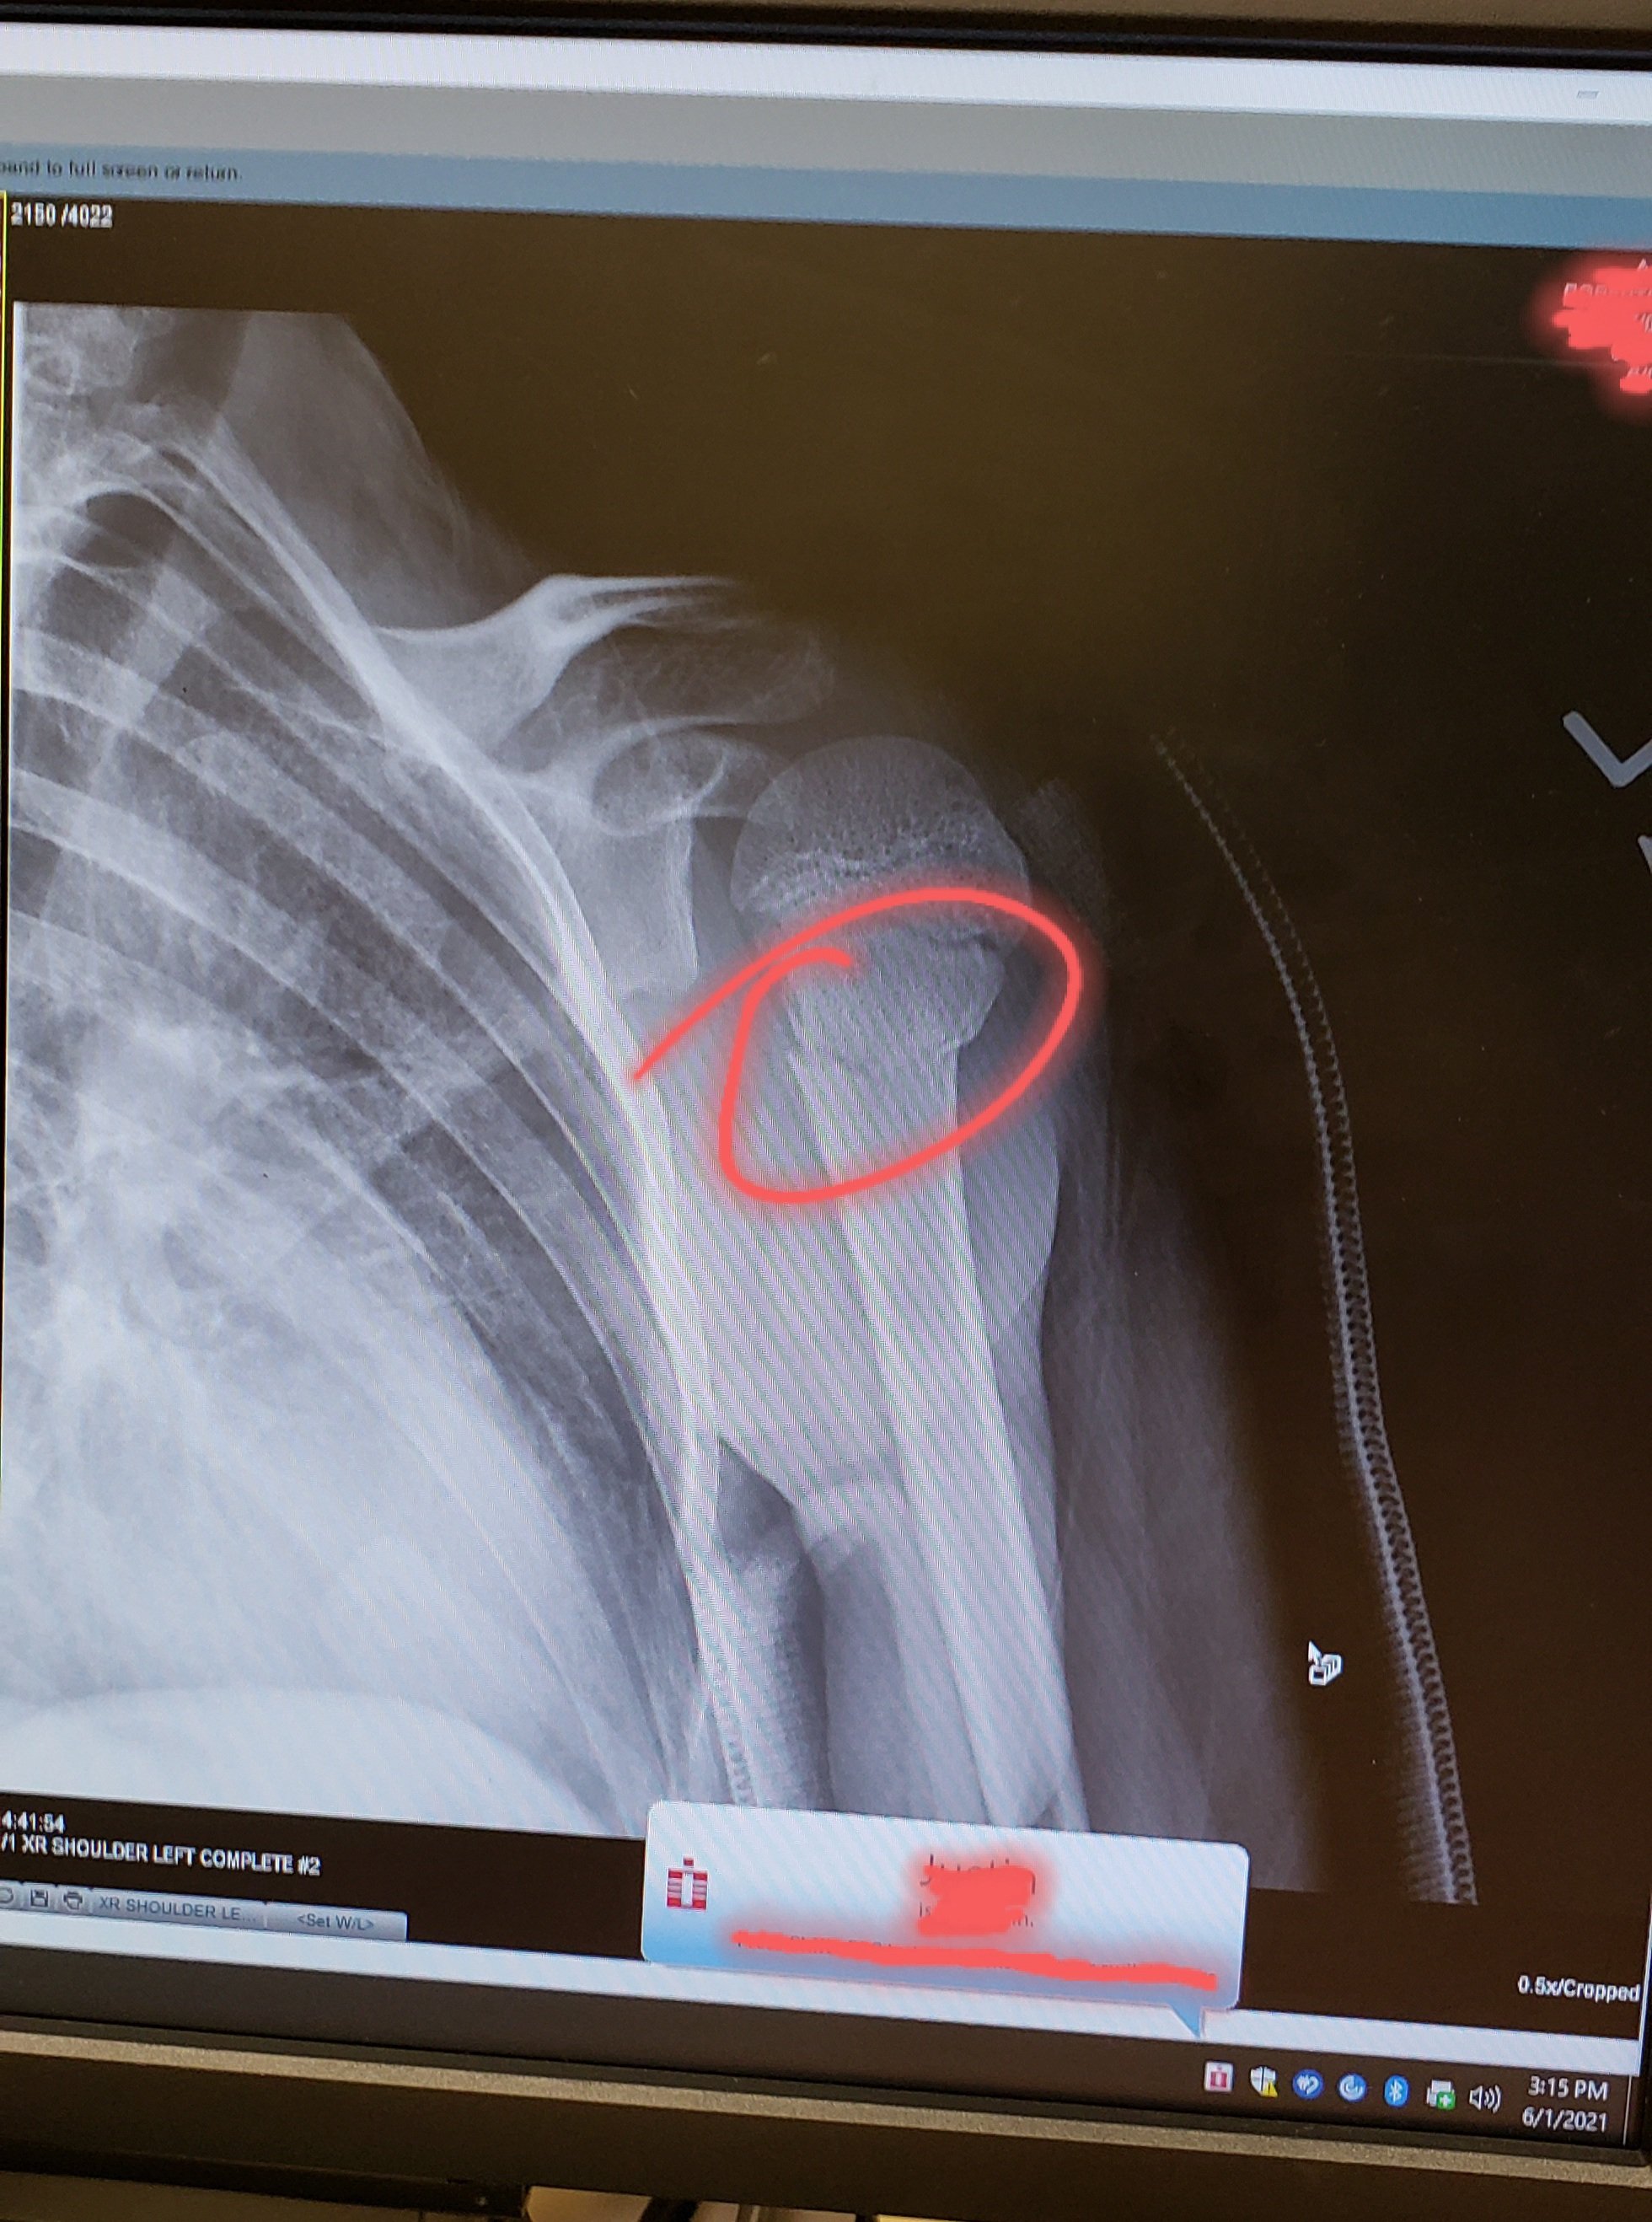

It seems that at some point of playing around. He thought it would be a good idea to do a front flip from the bouncy house opening to the slide that was build on. Not being able to stick the landing the way he wanted too. He did land on his arm and bend it backwards… After he was able to move, we took him the the local ER to see if there was more damage than we were seeing.

I believe we were at the ER for almost 3 hours. They did some x-rays and found that he did brake his arm and pulled a few muscles. They gave him a shot small of morphine to help with his pain and put a splint/sling on him. He did have nurse that was hilarious and had a number of dad jokes/dark jokes. Which is right up my son alley, Odin knows that kids loves his bad jokes hahaha. I have to say that kid on morphine is something to see hahaha. He did not stop talking and so, SO MANY JOKES. I wish I got it on video, just to focused on getting everyone home.